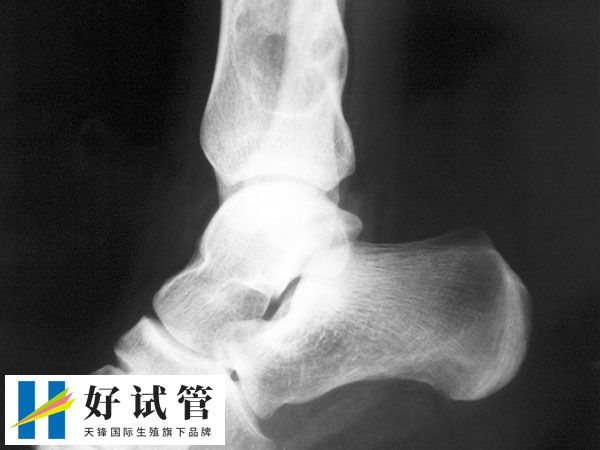

尽快前往正规医院的骨科或肿瘤科就诊,进行全面检查,包括影像学检查(如X光、CT、MRI等)和病理活检,以明确诊断和病情分期。